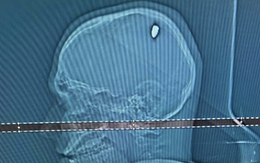

Chàng trai bị đạn ghim trong đầu 4 ngày mà không hay biết

Chẳng ai ngờ nam thanh niên vẫn "sống ổn" sau 4 ngày bị đạn ghim vào đầu. Thậm chí, anh còn lái xe "rần rần" hàng trăm km để đi "quẩy" cùng bạn bè.